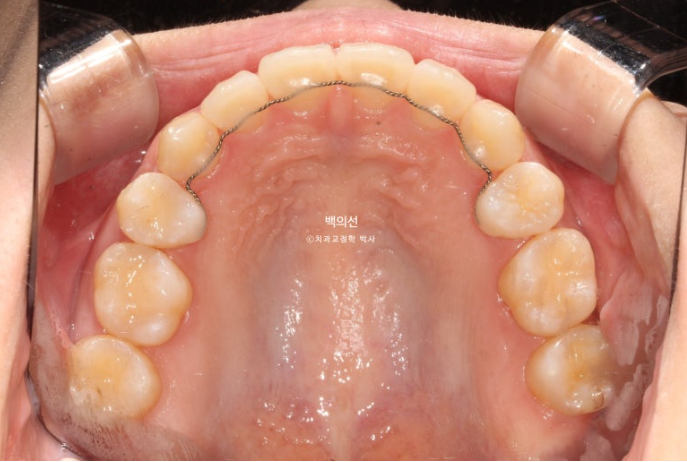

그리고 치료 시작 10개월차, 교합면 사진을 보면 마치 발치공간이 다 닫힌것 처럼 보입니다.

23.10

그러나 발치공간으로 어금니가 쓰러진걸 볼 수 있습니다.

쓰러진 어금니를 세우는 데에는 인비절라인이 효과적인 경우도 있고 브라켓이 효과적인 경우도 있습니다.

이 경우 쓰러진 정도가 심해 부라켓을 붙여 부분교정으로 쓰러진 어금니를 세우기로 합니다.

23년 10월부터 5개월간 어금니에 부분적으로 브라켓을 붙이고 나사를 심고 고무줄을 걸며 쓰러진 어금니를 세웠습니다.